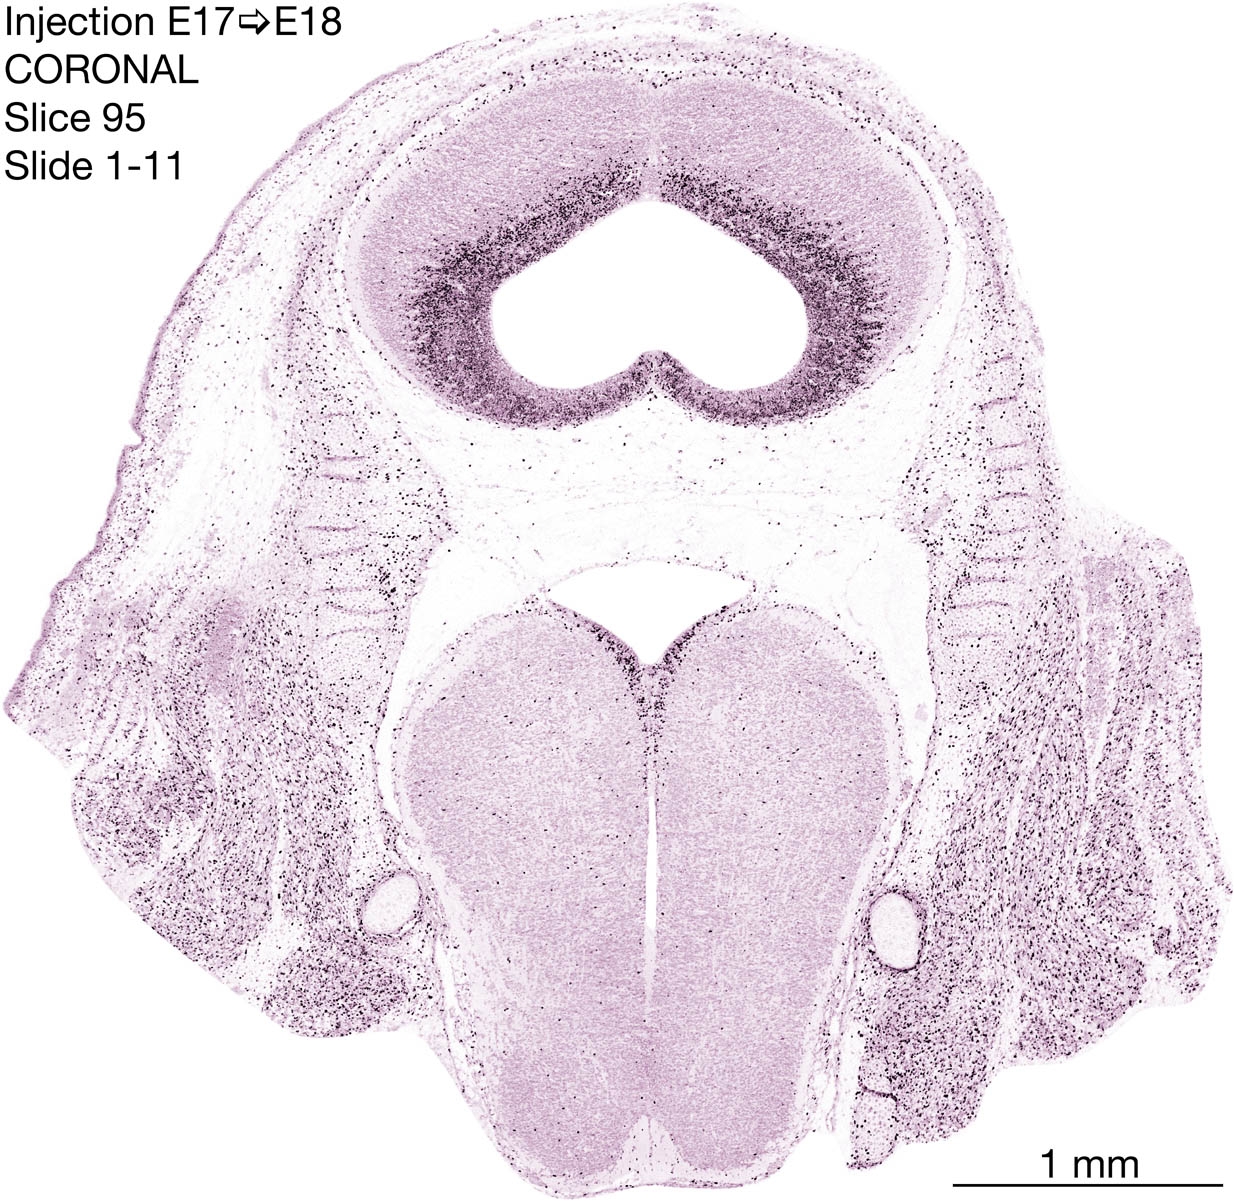

E17 to E18 Survival Archived Images-Coronal

The following images are from a coronally-sectioned head of an E18 rat embryo exposed to tritiated thymidine on E17–24 hr survival.  Note the heavily-labeled cells just outside the germinal zones are now mainly in the diencephalon and forebrain.  These are postmitotic young neurons generated ON E17.  Note that the banded labeling is prominent outside the neocortical neuroepithelium.  Many of the germinal zones in the brainstem have become transformed into the primitive ependyma, and the entire brainstem is becoming more mature; the only primitive area is the cerebellum, where the external germinal layer is now more prominent.